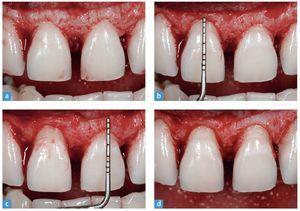

Fig. 16. a A fin de garantizar una reducción del esmalte mínima, se utiliza una llave de silicona. b Se emplea una sonda periodontal con la llave de silicona para el control del grosor de la preparación.

Figs. 17a a 17c. Vistas frontales y proximales tras la preparación mediante diamantes de tamaño medio.

El acabado y el pulido de la preparación son el requisito para obtener unos modelos precisos. Este paso de trabajo se lleva a cabo con un diamante fino, serie roja (n.º 8856 018, Brasseler). Éste posee la misma forma y el mismo diámetro que la fresa utilizada durante la preparación. El acabado de la preparación elimina todos los rasguños de la fresa previamente empleada (fig. 18). En la figura 19 se ofrece una vista detallada de la preparación extremadamente respetuosa. Tras el acabado se utilizan de nuevo las llaves de silicona para verificar la preparación (fig. 20). Los caninos se pulen únicamente para eliminar eventuales zonas retentivas que pudieran obstaculizar el ajuste de las carillas parciales.

Fig. 19. Tomas de detalle de la preparación de carilla extremadamente respetuosa. a Vista de los dientes anteriores superiores centrales antes de la operación; b el rebajado de la altura proximal de la forma; c después del rebajado proximal; d el inicio de la reducción; e la preparación terminada tras el pulido.

Figs. 20a y 20b. Se posiciona la llave de silicona y se comprueba de nuevo el espacio libre, a fin de garantizar una reducción ideal del diente antes de la restauración.